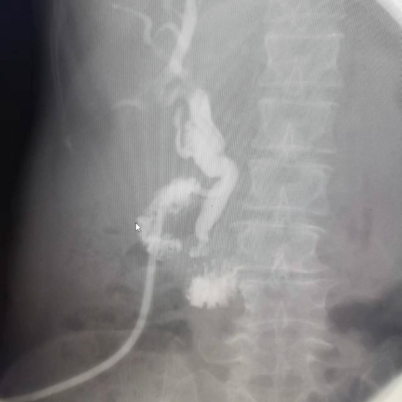

子宮輸卵管造影

實時觀察,有助確定病變類型及位置,檢查損傷小,刺激性小,能顯示子宮變異、子宮輸卵管通暢情況,并對疏通輸卵管有一定的治療作用。